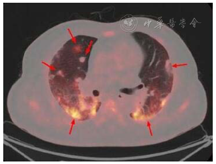

患者,男,56岁,因发热、咳嗽、咳痰伴活动后胸闷3 d于2019年9月10日入院。患者3 d前无诱因出现发热,体温在38 ℃左右,无畏寒、寒战,无盗汗,发热无明显规律性,伴咳嗽,咳少许黄白痰,无胸痛、咯血,伴胸闷、憋气,活动后加重,无消瘦,无头晕、恶心、呕吐,门诊行胸部CT考虑双肺感染性病变,为进一步诊治收住院。患者入院的20 d前在日本出差时出现咽痛,自服感冒药物(具体不详)后好转。既往有“冠心病、高血压”病史4年,2015年行冠脉造影示冠状动脉肌桥,无吸烟史,无禽类、粉尘、工业毒物接触史。体格检查:体温36.5 ℃,脉搏84次/min,呼吸23次/min,血压137/75 mmHg(1 mmHg=0.133 kPa),神志清,全身皮肤无皮疹,口唇发绀,双肺呼吸音粗,双下肺可闻及湿性啰音,心率84次/min,律齐,未闻及杂音。腹软,无压痛、反跳痛,双下肢无浮肿,四肢肌力正常。入院后查动脉血气分析(未吸氧):pH为7.374,二氧化碳分压为39.4 mmHg,氧分压为52.6 mmHg,血氧饱和度为84.8%,乳酸为1.1 mmol/L;血常规:白细胞计数为7.68×109/L,中性粒细胞百分比为 72.1%,淋巴细胞百分比为17.2%,红细胞计数为4.47×1012/L,血沉为16 mm/h;血生化:白蛋白为36.3 g/L,葡萄糖为6.44 mmol/L,乳酸脱氢酶为284 U/L,C反应蛋白为30.9 mg/L,三酰甘油为2.25 mmol/L;血凝常规:纤维蛋白原含量为4.67 g/L;肺肿瘤标志物CYFRA21-1为11.3 ng/ml;降钙素原为0.052 μg/L;病原学检查:半乳甘露聚糖试验(GM试验)为0.38 μg/L;痰细菌培养、真菌涂片、结核菌涂片阴性;肺炎支原体抗体、衣原体抗体、呼吸道合胞病毒抗体、出血热病毒抗体、真菌葡聚糖、巨细胞病毒核酸检测均阴性;免疫相关:抗核抗体(ANA)、抗环瓜氨酸肽抗体(CCP)、抗中性粒细胞胞浆抗体(ANCA)均阴性;机体细胞免疫评价正常;尿常规、大便常规、肌钙蛋白、脑钠肽均正常;乙肝表明抗原、丙肝抗体、梅毒抗体、HIV抗体均阴性;心电图示窦性心律、心电轴中度左偏、ST-T异常;胸部CT考虑双肺感染,建议治疗后复查,心影饱满,冠脉钙化,两侧胸膜略增厚(图1A~C)。入院后给予经鼻高流量湿化氧疗(氧浓度50.0%,氧流量50 L/min),美洛西林舒巴坦(2.5 g,1次/12 h)联合左氧氟沙星(0.6 g,1次/d)抗感染,奥司他韦胶囊(75.0 mg,2次/d)抗病毒,多索茶碱(0.3 g,1次/d)扩张支气管,溴己新(4.0 mg,2次/d)止咳化痰,低分子肝素钠(5 000 U,ih,1次/d)抗凝,硝苯地平缓释片(10.0 mg,2次/d)降压治疗,患者体温逐渐降为正常,但活动时胸闷无改善,经皮血氧饱和度在95.0% 左右(上述氧疗情况下),考虑抗感染解痉平喘治疗效果不佳,不除外间质性肺病,遂于9月14日加用甲泼尼龙(40.0 mg,1次/12 h)静滴,自觉症状略有好转,于9月17日复查胸部CT示双肺片状影较前增多(图2A~C),提示疾病进展,与患者及家属沟通后于9月17日行床旁支气管镜检查,镜下见左右肺各叶段支气管通畅,黏膜轻度充血,可见少量白色泡沫样分泌物,未见狭窄、出血及新生物(图3),于右肺下叶后基底段行肺泡灌洗及透壁肺活检,肺泡灌洗液(BALF)细胞分类示淋巴细胞百分比为63.0%,中性粒细胞百分比为24.0%,巨噬细胞百分比为8.0%,上皮细胞百分比为5.0%;BALF细菌、真菌涂片和培养均阴性;BALF结核菌涂片、结核菌核酸扩增检测(Gene Xpert)均阴性;BALF脱落细胞学检查阴性;BALF-GM试验0.55 ng/ml;BALF病原微生物宏基因组检测(NGS)示产黑色素普雷沃菌(序列数12)、龋齿罗氏菌(序列数7)、简明弯曲杆菌(序列数1);支气管镜肺活检病理考虑肺间质纤维化(图4)。患者对治疗反应不佳,为排除肿瘤于9月20日行正电子发射计算机断层显像(PET-CT)示双肺多发斑片影、结节灶,大部分见支气管充气征,部分结节边缘见分叶和毛刺,SUVmax 6.4,考虑感染性疾病,霉菌感染可能性大,肉芽肿性炎和MALT淋巴瘤不除外(图5)。请北京协和医院专家会诊,考虑ILD,不除外结缔组织病相关,建议加大甲泼尼龙(80.0 mg,1次/8 h)用量,升级抗生素为美罗培南(1.0 g,1次/8 h),完善肌炎谱13项示抗Jo-1抗体阳性,最终诊断为抗Jo-1抗体综合征,加用环磷酰胺(0.4 g,1次/周)静滴8次,并逐渐减少甲泼尼龙用量,患者胸闷症状明显好转,2019年11月18日复查胸部CT示肺内病变较前明显吸收好转(图6A~C),随访1年,病情稳定。